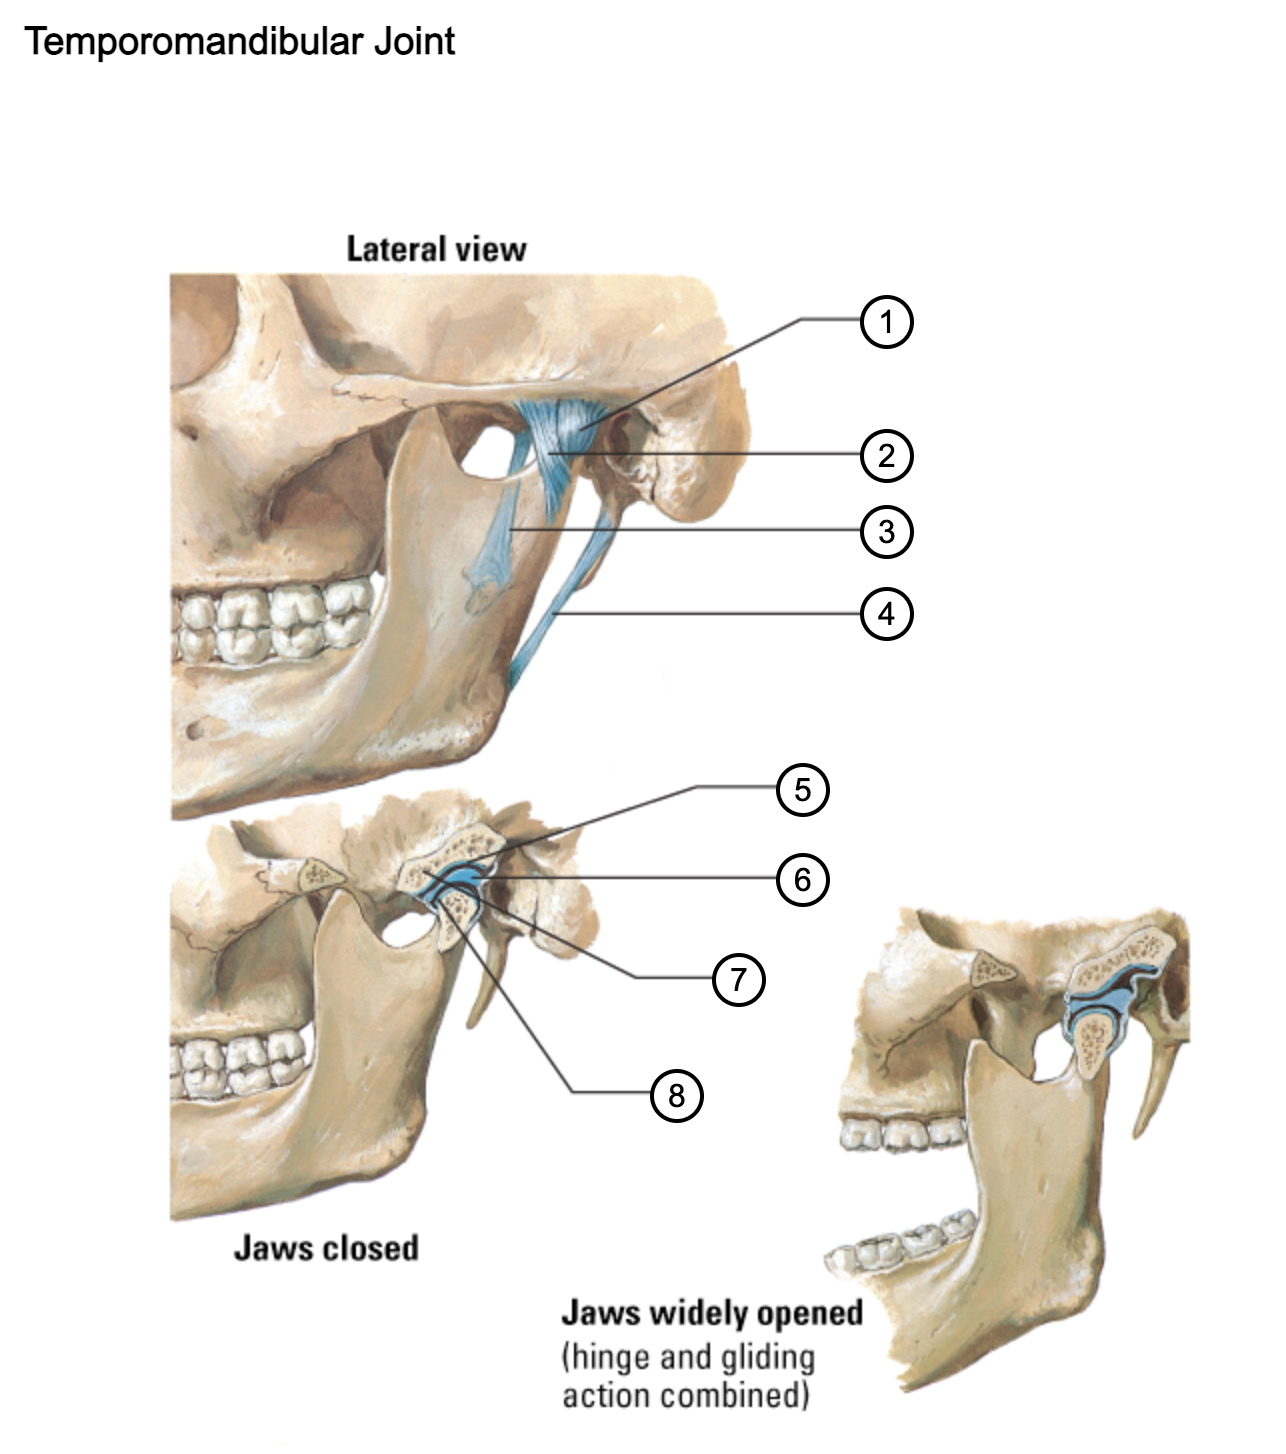

1

capsule of temporomandibular joint

2

lateral temporomandibular ligament

3

sphenomandibular ligament

4

stylomandibular ligament

5

mandibular fossa

6

articular disc

7

articular tubercle

8

capsule of temporomandibular joint